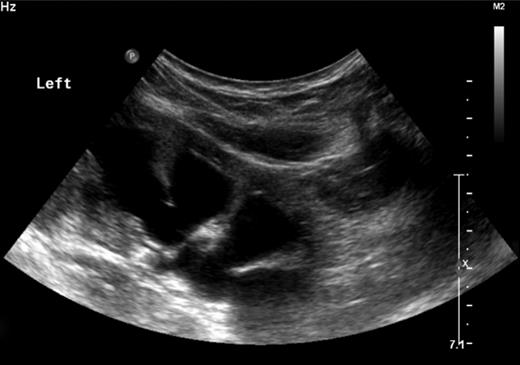

Repeated measurements of his blood pressure showed a lowest blood pressure of 148/90. As per the fourth report; any blood pressure above 109/65 for this 3-year-old child meets the criteria for hypertension [1]. On more direct questioning, the mother reported that the child always had a poor urinary stream. An urgent ultrasound of the child's urinary tract showed gross hydronephrosis bilaterally with calyceal dilatation (see Fig. 1).